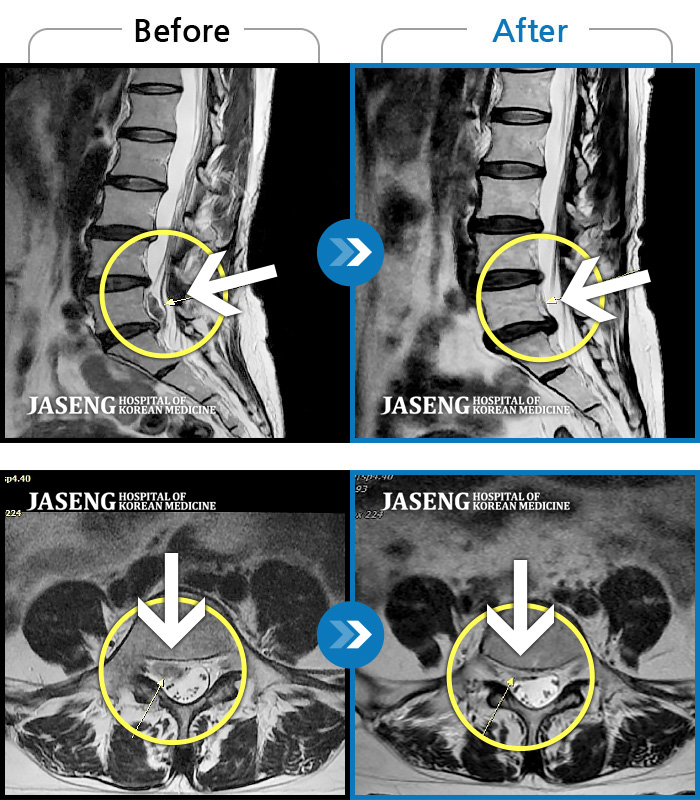

허리디스크

울산 · 정운석 원장

양측 하요추부 통증과 우측 하지 저림

촬영시기

2022.03.16 ~ 2022.11.12

2023.01.19